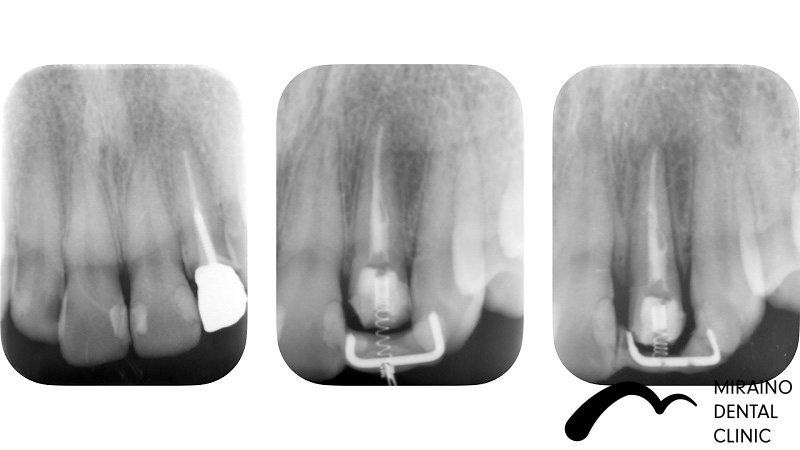

歯の破折予防:MTMの症例

| 施術名 | 歯の破折予防:MTM |

| 施術の概要 | 前歯の差し歯の色が気になるということで来院されました。 噛んだ時に下の前歯が隠れており、治療した歯をより劣化させやすい噛み合わせ[過蓋伵合]の方でした。 歯を失う原因のうち、ムシ歯・歯周病以外に歯への負担荷重お伝えしましたが、 根本的な噛み合わせの治療は希望されなかったため、 次回再発した際は抜歯となる可能性が高いため、なるべく再発しにくい歯科治療を希望され、 MTMを行ったのちメタルフリークラウンでの歯冠修復行いました。 |

クリックして詳細を表示

| 施術の内容 | ムシ歯や歯が折れておりで感染除去後に健康な歯が歯茎の下まで達する場合は、 通常、抜歯もしくは2年以内の抜歯前提の延命治療になってしまいます。 両サイドの歯に表装置をつけ骨からひっぱり出すことで、 歯根破折・歯冠脱離による抜歯の可能性を回避します。 部分矯正MTM(Minor Tooth Movement)の略で、 このような場合エクストルージョン(伾出)と言います。 |

|---|---|

| 1歯あたりの治療費 | 1歯につき50,000円 |

| 考えられるリスク、副作用[歯科治療] | 治療後、痛みや違和感、出血、腫れ、麻痺などが出る事があります。 |

| 考えられるリスク、副作用[全てにおいて] | 必ずしもご希望通りにならない事があります |

| 考えられるリスク、副作用[麻酔] | 麻酔を行う場合、腫れやむくみを生じる事があります。 |

| 考えられるリスク、副作用[噛み合わせ] | また、歯並びが変わる事により違和感を生じる事があります。 |

| 考えられるリスク、副作用[被せ・仮歯] | 仮歯の期間中は仮歯の部分で噛むと破損する場合があります。 |

| 考えられるリスク、副作用[根の治療] | 治療に際して、根の治療が必要になる場合があります。 |